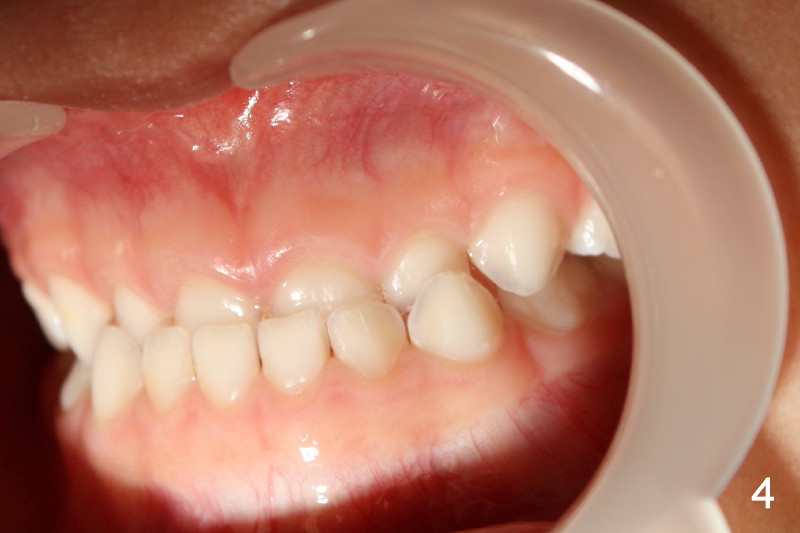

Right canine occlusion is Class I (Fig.3), whereas left Class III (Fig.4).